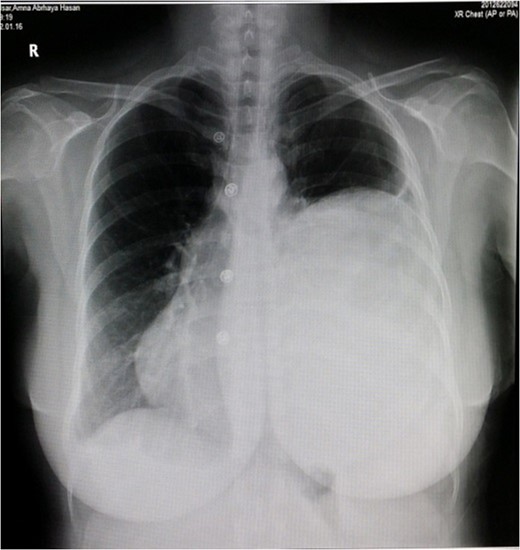

Chest x-ray showed well-defined huge opacity of most left hemithorax with a shift of mediastinum to the right (Fig. 1). CT chest/abdomen/pelvis with IV contrast revealed 20 × 15 × 18 cm3 well-defined mixed cystic lesion within the left lung containing multiple parts of the heterogeneous density with soft tissue elements and fat content. It also showed spots of wall calcification, where the lesion probably originated from the mediastinum, involving most of the left hemithorax. The mass compressed the mediastinal structures, great vessels, and airways (Fig. 2). It is surrounded by a consolidation collapsed with a marked shift of mediastinum to the right side (Figs 2 and 3). No mediastinal lymphadenopathy and the right lung was clear. The spleen was enlarged with multiple cysts that varied in size with no significant enhancement post IV contrast in arterial and portal phases (Figs 2 and 4). The liver was unremarkable. Hematological tests were within normal limits. Mantoux test and Sputum culture were negative.